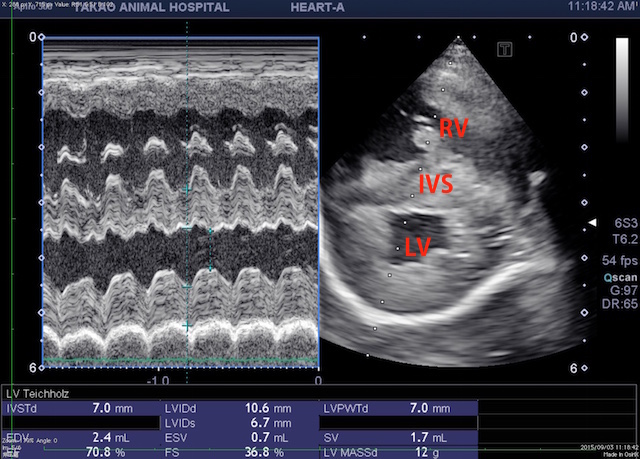

エコー検査を行うと心室中隔の扁平化が起こっており、右心室に圧負荷があることが疑え、肺動脈の狭窄などもないことから、肺高血圧症が疑われました。

(RV:右心室 IVS:心室中隔 LV:左心室)